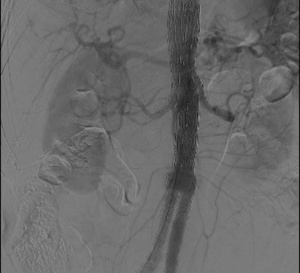

L’intelligence artificielle pour le suivi des patients bénéficiant d’une endoprothèse aortique 03/03/2022

L’endoprothèse a révolutionné le traitement des anévrysmes aortiques : au lieu de pratiquer un geste chirurgical enlevant l’anévrysme, il s’agit d’exclure celui-ci en posant un stent, qui l’élimine...